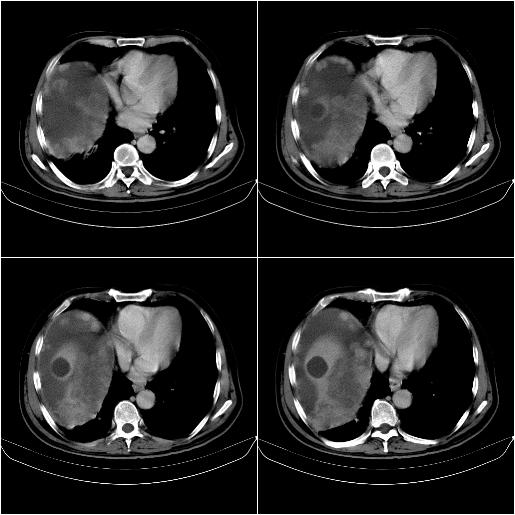

标题: CT21651:M,67Y,肝癌9月,介入术后3月。

m,67y,肝癌9月,介入术后3月。现腹胀、纳差、腹泻。

门静脉有很大的瘤栓,膈肌及膜膜有转移,不用再做了.

1)肝癌介入治疗术后碘油沉积不良。2)门静脉瘤栓形成,腹膜广泛性转移。3)肝硬化,脾大,腹水。4)慢性胆囊炎。